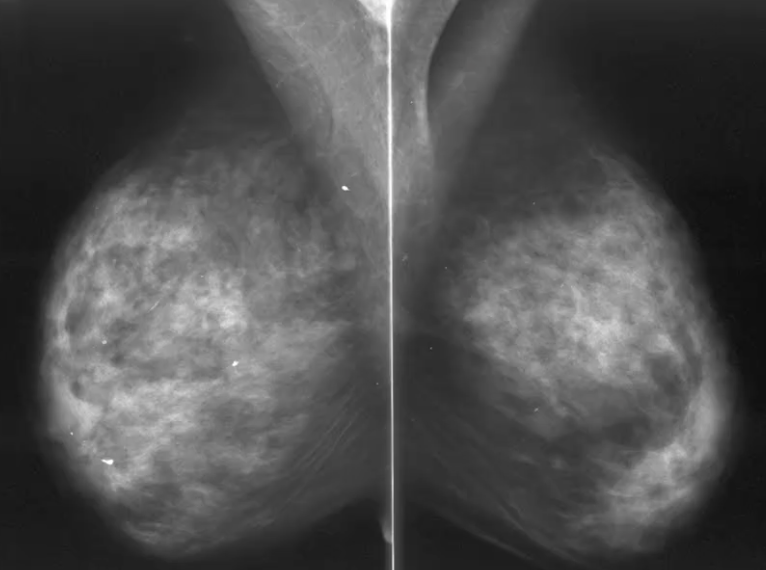

What is this an image of?

Dense breast tissue - more difficult to see breast cancers